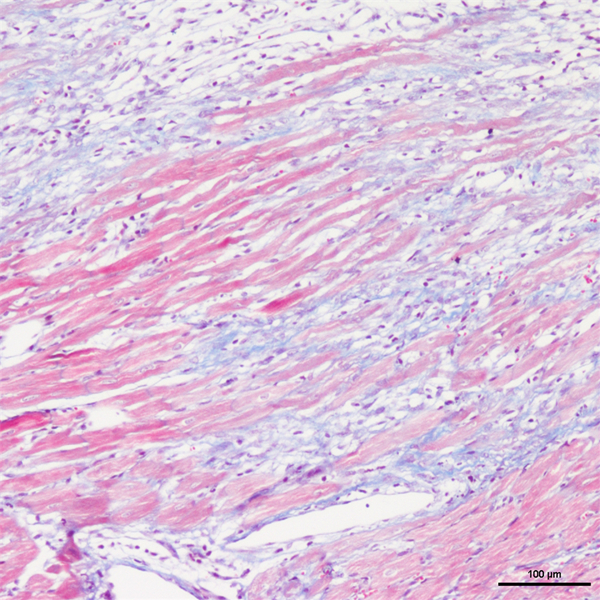

Masson染色

丽春红酸性品红-苯胺蓝染色,是用于检测动物组织中胶原纤维的一种染色方法之一,能够将胶原纤维染成蓝色,肌纤维、和红细胞呈红色,可用于鉴胶原纤维和肌纤维;并显示各种组织胶原纤维含量及纤维化程度。

Masson染色时胶原纤维呈蓝色(被苯胺蓝所染)或绿色(被亮绿所染),肌纤维呈红色(被酸性品红和丽春红所染),这与阴离子染料分子的大小和组织的渗透性有关。如已固定的组织用一系列阴离子水溶性染料先后或混合染色,则可发现红细胞被最小分子的阴离子染料着染,肌纤维与胞质被中等大小的阴离子染料着染,而胶原纤维则被大分子的阴离子染料着染。由此说明了红细胞对阴离子染料的渗透性最小,肌纤维与胞质次之,而胶原纤维具有最大的渗透性。根据组织不同的渗透性能,选择分子大小不同的阴离子染料进行染色,便可把不同组织成分显示出来。

<masson-心梗>